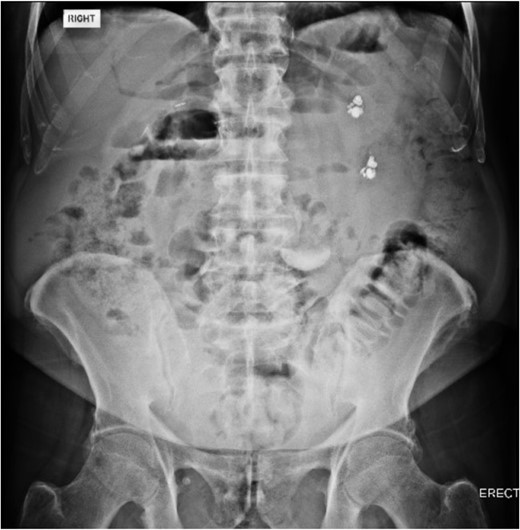

During the push enteroscopy the hearing aid could not be found despite thorough inspection of duodenal diverticula. The procedure was assisted by image intensifier guidance, and upon consultation with the onsite radiologist, the impression was that the hearing aid was in a jejunal diverticulum rather than a duodenal diverticulum. The procedure was abandoned and a single balloon assisted enteroscopy was planned for the following day. Prior to the procedure, the foreign body could not be located on the initial scout x-ray, and it was presumed to have passed naturally. Follow up formal x-rays again did not identify a foreign body (Figs 4 and 5), and the patient has been well since.